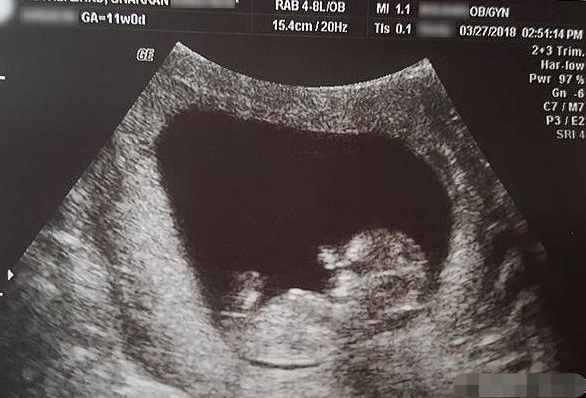

胎儿80天

这个是我怀孕80天的b超,不知道是男孩女孩,有会看的吗?

怀孕后想知道婴儿性别,检查单上有这四个字,是男孩的几率大